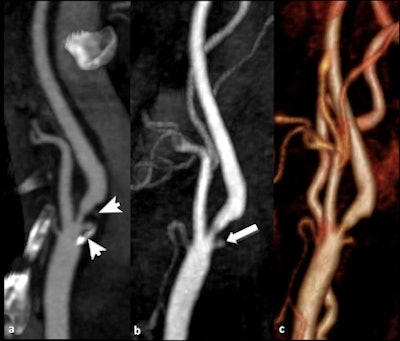

![]() |

| Patient with dissection of brachiocephalic arterial trunk and right common carotid artery. A, B: Time-resolved sequences allow the visualization of an asymmetric transit time of the contrast agent, showing delayed opacification of right common and internal carotid artery compared to the normal left vessels. (Provided by Prof. Carlo Catalano and Dr. Beatrice Cavallo Marincola) |